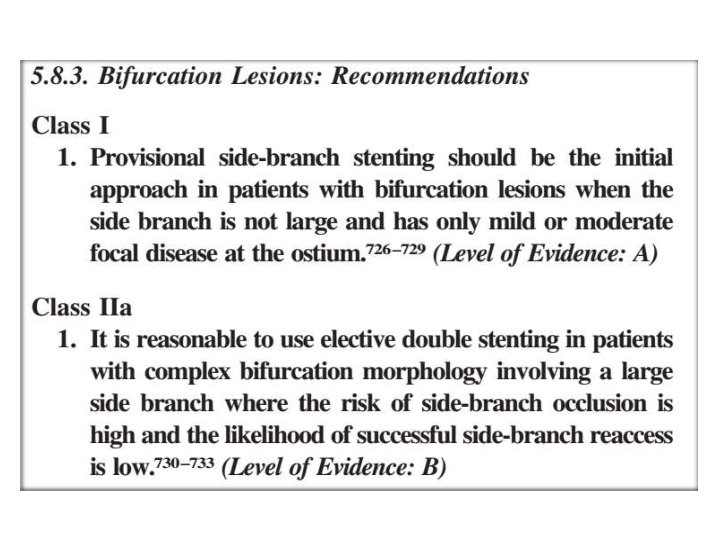

One vs two stents • • • Important trials NORDIC 2 BBC CACTUS

When to use elective two stents?

1. Nordic I: provisional T stenting as good as systematic side branch stenting 2. Nordic II: Culotte better than Crush 3. Cactus: provisional T stenting not worse than crush 4. BBC ONE: step wise approach with provisional T stenting better than initial complex procedures 5. Bad Krozingen: no difference provisional vs systematic T 6. Double Kiss Crush Study: DK Crush better than conv. crush Steigen Circulation 2006; 114: 1955; Erglis TCT 2008; Hildick-Smith TCT 200 Ferenc EHJ 2009; Chen JInterv Cardiol 2009; 22: 121 -27